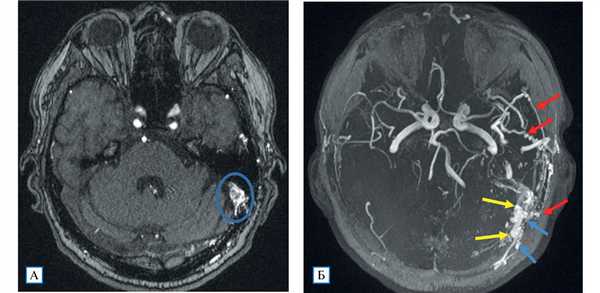

Проведенное дуплексное сканирование сосудов головы обнаружило признаки артериовенозной мальформации в бассейне левой наружной сонной артерии с артериализацией и усилением кровотока по внутренней яремной вене. Усиление скорости кровотока по задней околоушной артерии позволило предположить ее в качестве «питающего» сосуда (рис. 1). Контрастная МР-ангиография подтвердила наличие артериовенозного соустья с вовлечением поперечного и частично сигмовидного синусов слева (рис. 2).

Рис. 2. МР-ангиография (3D TOF-ангиография)

Примечание. А — сброс крови из ветвей наружной сонной артерии в левый поперечный синус; Б — аксиальная MIP-реконструкция: визуализируются нормальные артерии Виллизиева круга; слева расширенные и извитые ветви наружной сонной артерии (алые стрелки), из которых происходит сброс крови в поперечный и сигмовидный синусы (желтые стрелки), извитость и расширение дуральных вен вследствие полнокровия (голубые стрелки).

Пациент консультирован нейрохирургом, запланировано эндоваскулярное лечение фистулы.